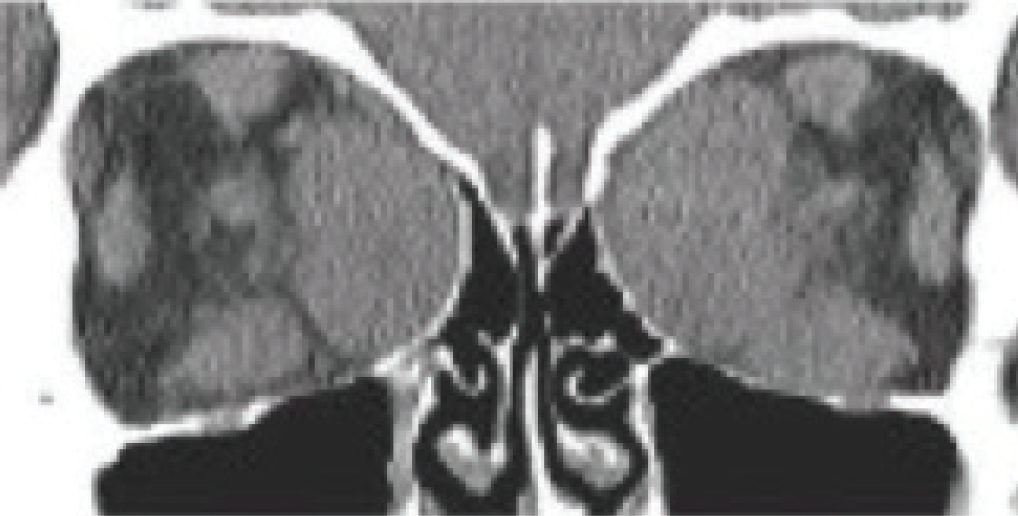

Figure 7. Postoperative coronal CT scan showing strategic removal of the entire medial wall, floor, and lateral wall of the left orbit with prolapse of the orbital contents through the osteotomies.

Many times, medical therapy may reduce the disease burden in TED but not restore orbital and ocular function to the predisease state (Figures 5 and 6). As a result, rehabilitative surgery may be required. Unless the risk of permanent eye damage is suspected, orbital and periocular surgery should be avoided during the active phase to ensure the stability of surgical results. Surgical techniques and instrumentation have been greatly improved, now allowing surgery to be tailored for each patient. Preoperative orbital volumetric and orbital physiologic analysis may provide the adaptive surgeon the ability to better predict surgical outcomes. The introduction of intraoperative surgical navigation and instrumentation, such as piezoelectric bone removal systems, may afford safer, more strategic outcomes with orbital decompression (Figure 7). Algorithms developed for strabismus and eyelid surgery may improve ocular function and appearance.